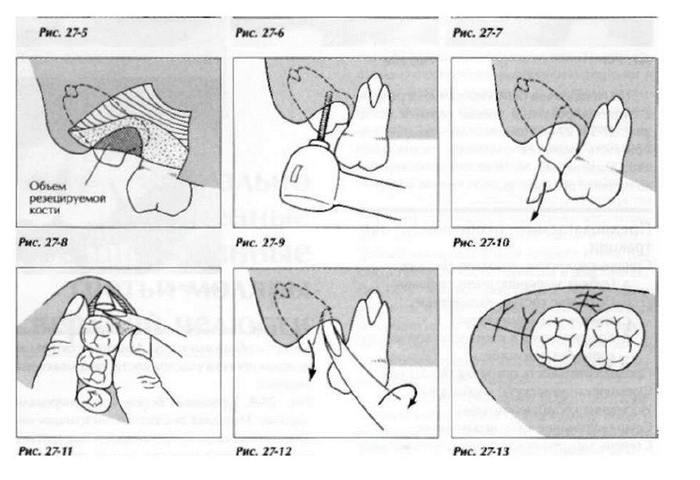

После того, как мы сделали анестезию, мы по необходимости производим разрез и отслаиваем слизистую оболочку с надкостницей от кости (слизисто-надкостничный лоскут) и бормашиной с водяным охлаждением выпиливаем костную стенку. Почему по необходимости? Потому что эти этапы зависят от степени прорезанности и расположения зуба. Чем более прорезан зуб, тем меньше разрез и меньше убираем кости. Иногда обходимся одним разрезом, иногда даже разрез не приходится делать, а просто распиливаем зуб. Короче, смотрим по ситуации.

По необходимости распиливаем сам зуб. Опять по необходимости? Конечно! Ведь надо смотреть по ситуации и соблюдать баланс между травматичностью и скоростью проведения операции. Если зуб лежит только под слизистой, корни сросшиеся и его можно достать элеватором, то не надо лишний раз его пилить. Достали, зашили и отпустили домой. Если же у нас зуб лежит криво и достать него просто так не получается, то тогда уже пилим либо зуб, либо подпиливаем кость.

Самое главное, чтобы в процессе удаления зуба не прилагалась большая сила. Потому что если мы будем прилагать большое усилие при извлечении зуба их кости, то в лучшем случае мы обломаем корни и будем возиться целый час с ними, а в худшем, вывихнем соседний зуб, а если врач весь интеллект перекачал в силу, то и перелом челюсти. Те, кто считает, что для удаления зубов нужна сила глубоко заблуждаются. Девочка метр с кепкой и в прыжке может удалять зубы в 100 раз быстрее, безболезненнее и аккуратнее, чем амбал. Тут главное мозг и аккуратность.

Если у зуба растопырены корни, то их тоже надо разделять и по одному доставать, как в 30 главе.

После того как все удалили, мы чистим лунку от опилок и осколков, убираем оболочку фолликула, если он имел место быть, моем антисептиком. Обязательно пальцем щупаем на предмет острых краев лунки, чтобы потом они не прорезались. Если торчат, то убираем.

Если мы резали и откидывали слизисто-надкостничный лоскут, то кладем его обратно, и фиксируем швами. После швов обязательно контролируем остановилась ли кровь. Поэтому если врач сказал, что шов последний, не надо резко вскакивать и убегать.

Посложнее